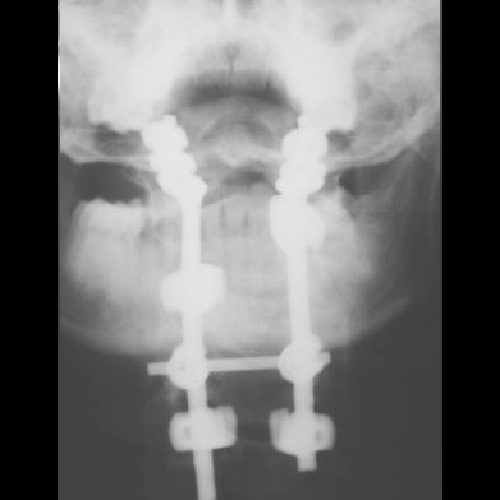

Титановая конструкция для окципитоспондилодеза Тип 1

Конструкция состоит из шейных ламинарных крючков, затылочных крючков, затылочно-шейного стержня, блокирующих гаек и поперечной стяжки (коннектор).

Для задней фиксации верхнешейного отдела позвоночника при его тяжелых повреждениях и заболеваниях.